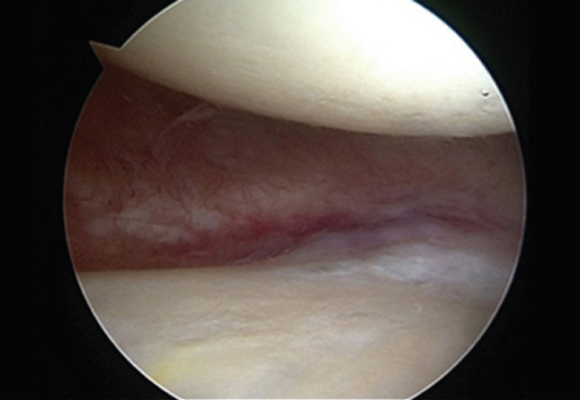

연골판봉합술

혈관이 있는 부위에 파열이 발생한 경우 연골판을 봉합해 주는 수술 시행

ㆍ환자 동의를 받은 자료이며, 이미지 사진은 실물과 다를 수 있습니다. (22.06.09)